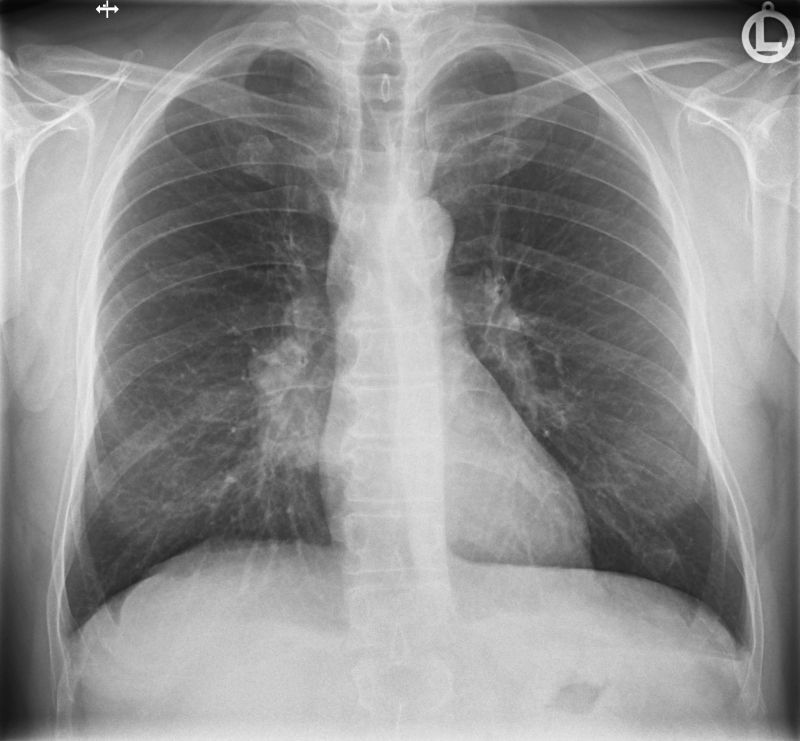

Röntgen der Lunge

Die Röntgenaufnahme der Lunge wird typischer Weise im Stehen am Wandstativ in zwei Ebenen in der Regel unter tiefer Einatmung durchgeführt. So können Veränderungen in der Lunge festgestellt und lokalisiert werden wie z.B. Tumoren, Lungenentzündung, Belüftungsprobleme von Lungenabschnitten und etliche andere Erkrankungen.